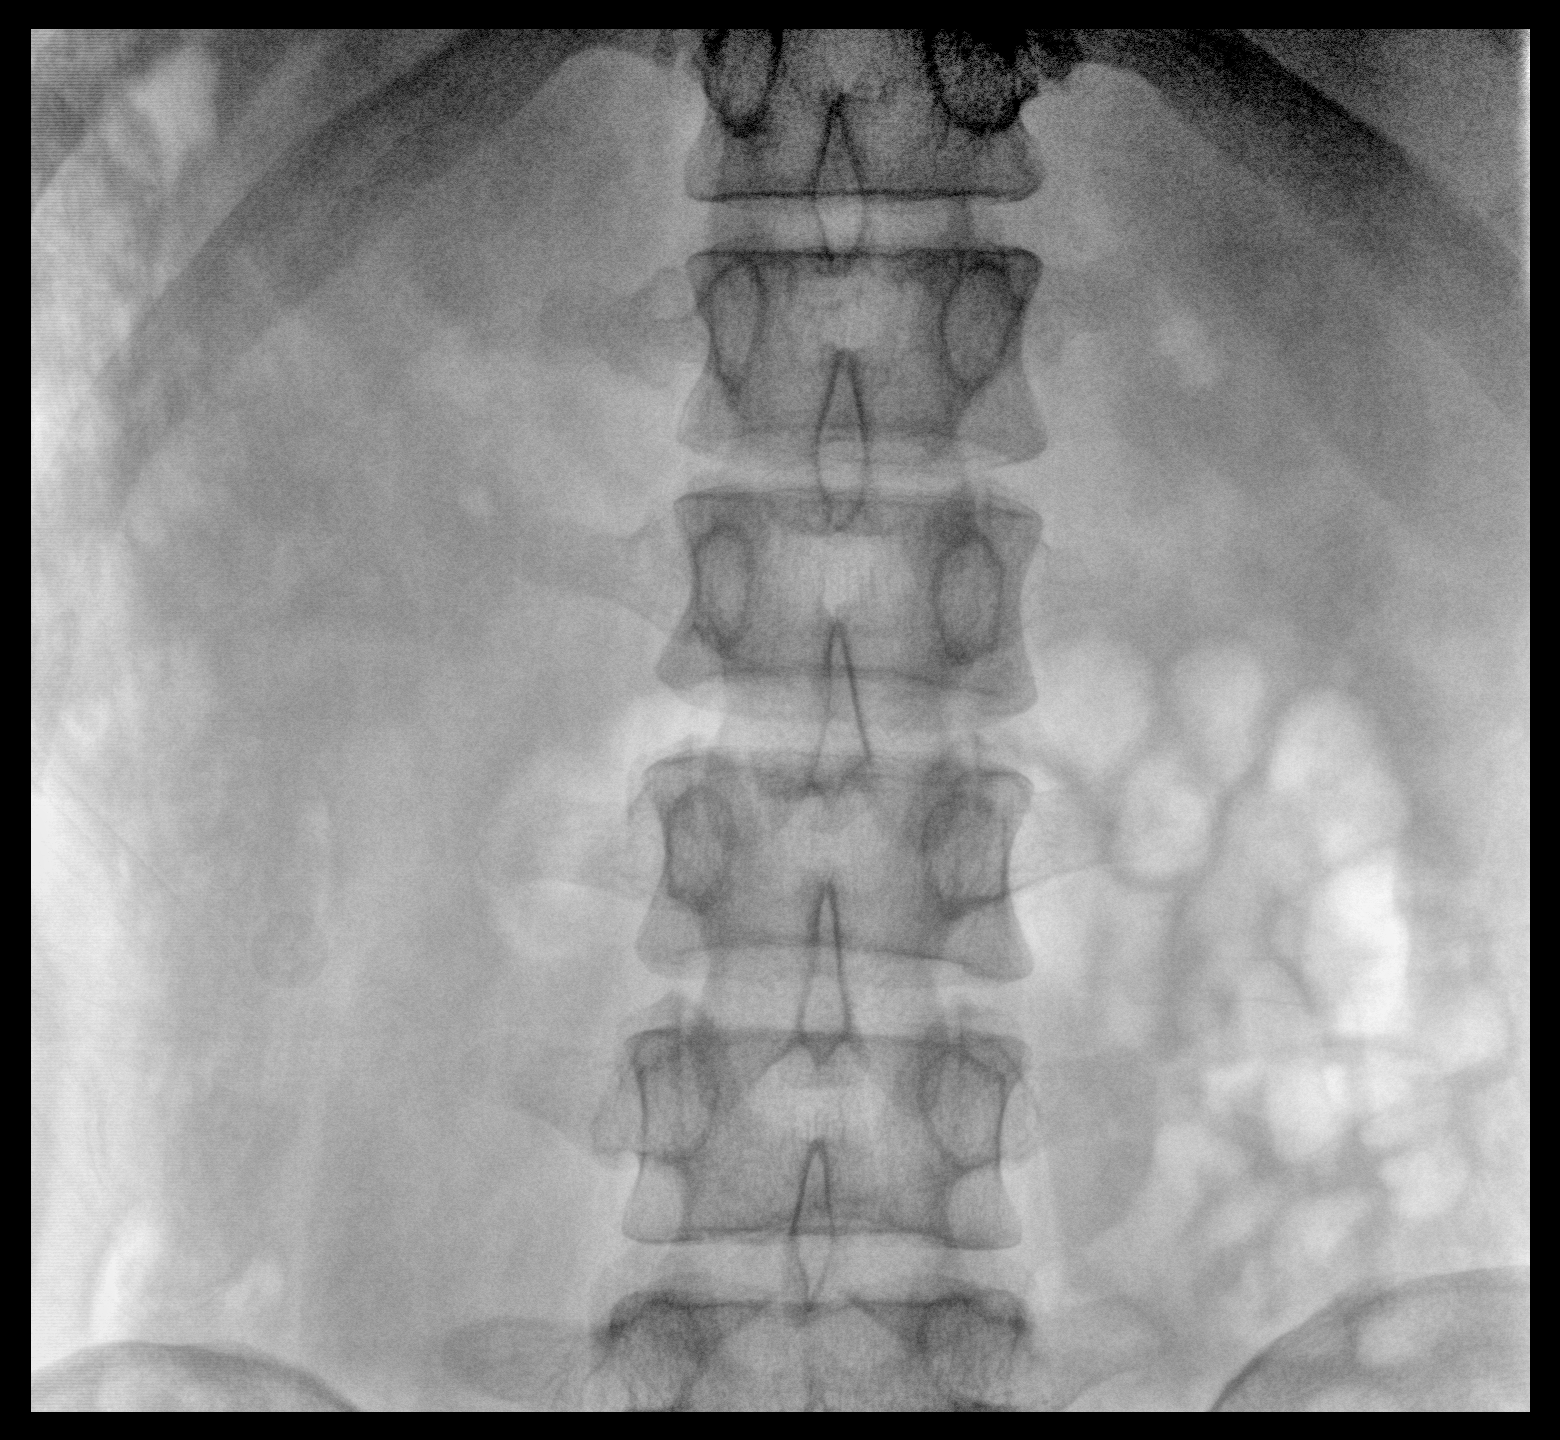

大尺寸動態(tài)平板探測器,高DQE、低噪聲、圖像清晰。采用多分辨率圖像增強處理技術(shù),不同部位不同圖像處理算法,滿足客戶多樣化的需求。

采用智能變頻脈沖透視技術(shù),優(yōu)化圖像質(zhì)量的同時降低輻射劑量,呵護醫(yī)患健康